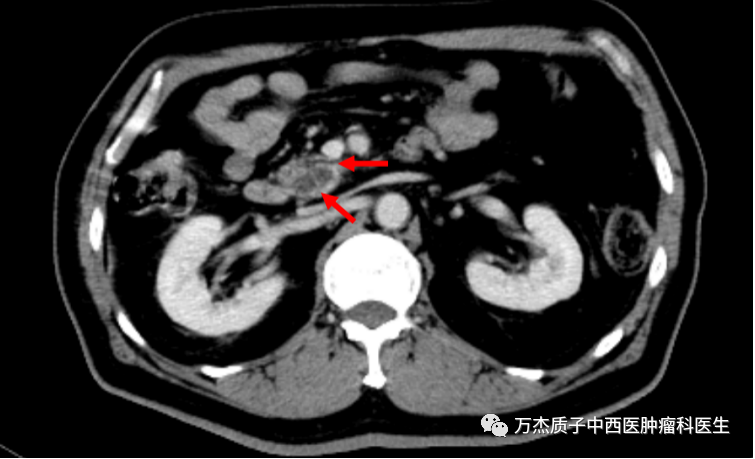

下图为质子治疗前肿瘤病灶显示情况,箭头所指处为胰腺肿瘤病灶